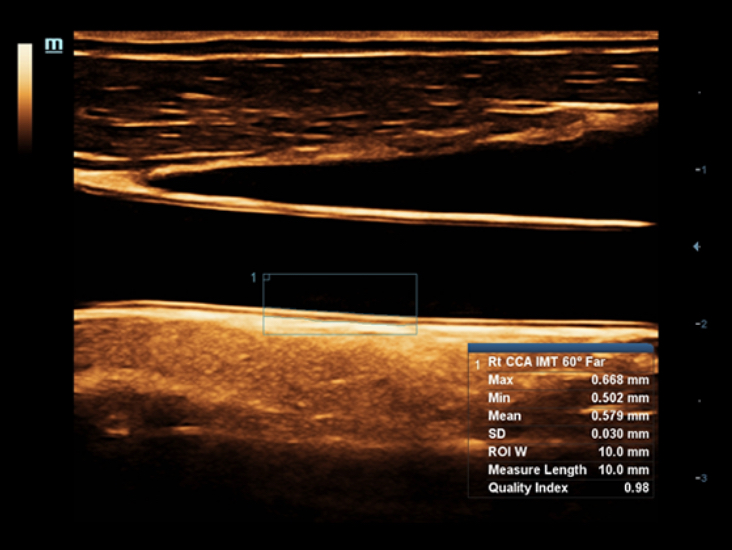

Sobre la base de un profundo conocimiento de las necesidades del cliente, el DC-60?ECHO con X-Insight estå dise?ado para brindar alta eficiencia con imågenes precisas, lo que se ve potenciado con eXpress Clarity (claridad exprés), eXceptional Intelligence (inteligencia excepcional) y eXceeding Experience (experiencia extraordinaria).